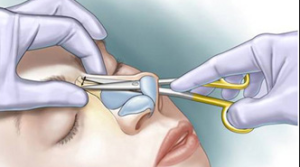

Burun Estetiği Kapalı Teknik

Kişisel tecrübeme gelince ameliyat sonrası şişliklerin daha az olması, dokuları daha az travmatize etmesi gibi düşüncelerle ilk planda kapalı tekniği tercih etmekteyim. Ancak hastanın burun deformitesi özellikle burun ucuna yönelik ağırlıktaysa veya çok detaylı bir cerrahi girişim yapılacaksa açık tekniği tercih etmekteyim. Ancak tecrübelerime göre kapalı teknik ile açık tekniğe gerek kalmadan bir çok hastanın sorunu çözülebilmektedir.